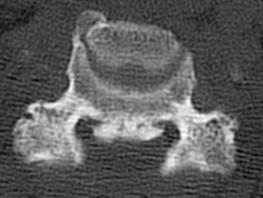

问题 女,58岁,颈部疼痛,活动受限,请结合图像,选出最可能的诊断 ( )

选项 A、椎间盘突出 B、局限性骨化性肌炎 C、颈椎结核 D、椎缘骨 E、颈椎退行性变

答案 E